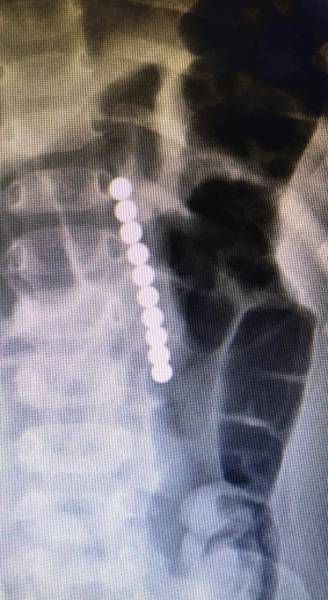

تمكّن فريق طبي في مستشفى الولادة والأطفال في الأحساء من استخراج سبحة مغناطيسية، من داخل بطن طفل يبلغ من العمر سنتين، حيث كان يعاني من قيء متكرر وآلام حادة في البطن، وبعد إجراء الفحص الطبي والتحاليل والأشعة اللازمة وجدت سبحة مغناطيسية في بطن الطفل، مما سبب له عدة ثقوب داخل المعدة والأمعاء الدقيقة، وقرر الفريق الطبي على إثرها إجراء عملية جراحية عاجلة، وتكللت بالنجاح ولله الحمد، حيث تم استخراج السبحة وإصلاح الثقوب وغادر الطفل المستشفى وهو بصحة جيدة.

استخراج «سبحة» من بطن طفل في «ولادة الأحساء»